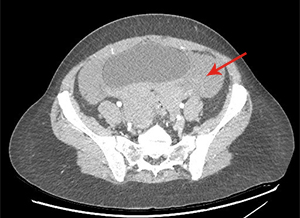

There is a large hemoperitoneum (arrow below) with a massive rectouterine structure (star below) concerning for clot.

We were most concerned about a ruptured ovarian cyst as the patient’s pregnancy test was negative and there was no other obvious cause of blood in the abdomen. She did not have the classic story of onset of pain after intercourse. We did a CT scan because the bedside ultrasound images were difficult to interpret due to the clotted blood. The radiologist suspected ruptured ovarian cyst as the cause of the hemoperitoneum.